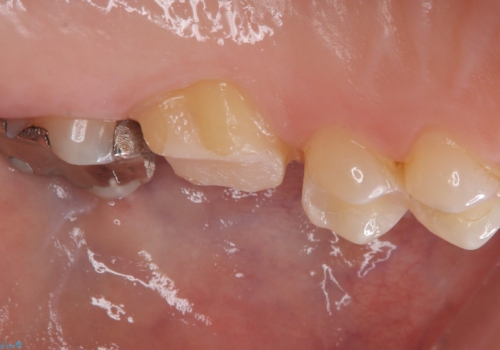

- 主訴:銀の詰め物を白くしたい

保険メタルインレーの入っている歯に虫歯が認められたため、セラミッククラウンでのやり替えとなりました。

左上6の近心にカリエスを認め、残存歯質と破折リスクの観点からセラミッククラウンでのやり替えとなりました。

今後ホワイトニング行う予定のため、シェード明るめにしています。